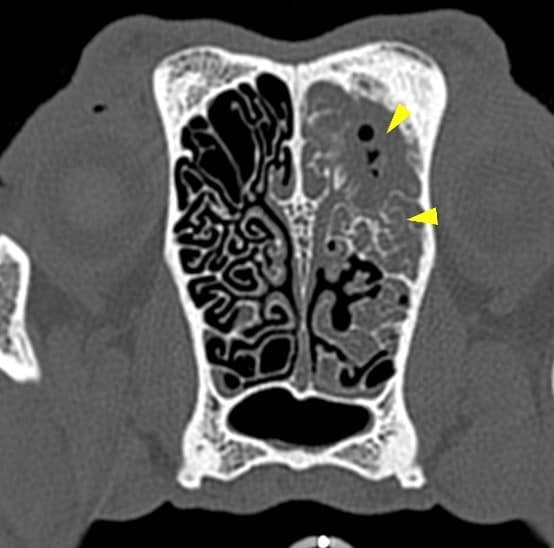

A large amount of fluid was occupying the caudal aspect of the left nasal cavity (yellow arrowheads). There was no lysis of the nasal septum, vomerine groove, ethmoid bone or cribriform plate. The left frontal sinus contained a large amount of fluid-attenuating material, surrounded by a severe ‘lamellar’ periosteal reaction (blue arrowheads).